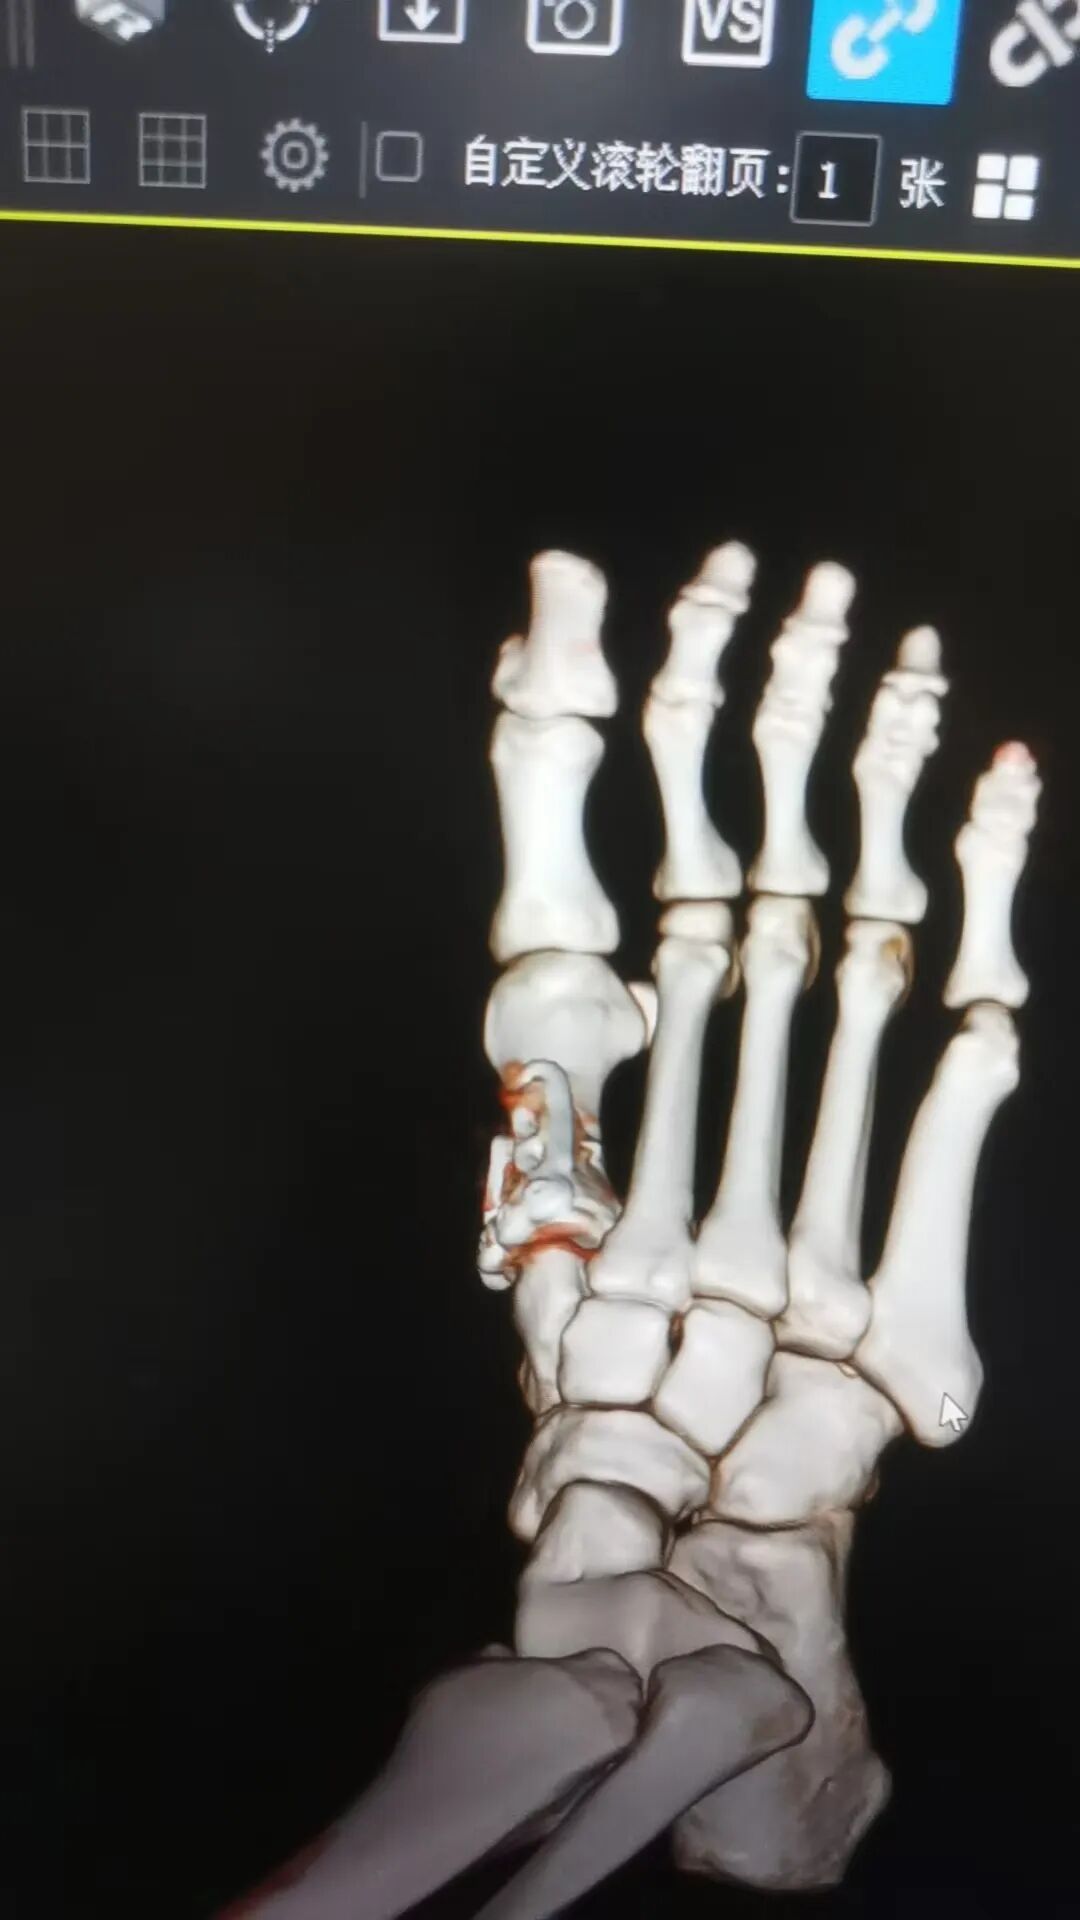

据悉,今年春节假期期间,家住南丹县的唐女士在行走时不慎跌倒,伤及右足部,伤后即感右足部呈持续性胀痛,右脚不能站立及行走,在家休息一天后,患处肿痛未缓解,遂至市中医医院骨伤科一病区就诊。经医生查体并行DR等辅助检查后,唐女士被诊断为“右足第一跖骨骨折”收治入院。

△术前

△术后